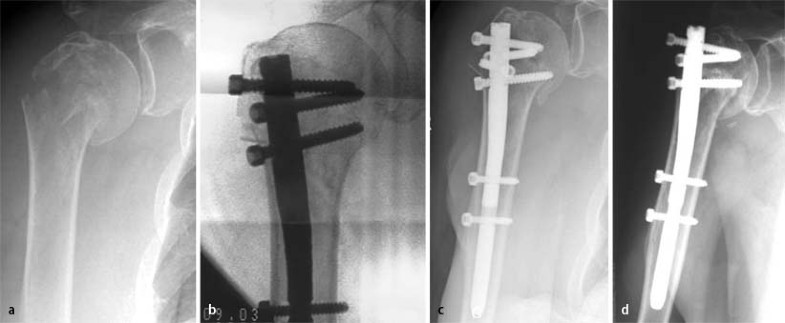

81-jährige Patientin nach häuslichem Sturz, a Röntgen am Unfalltag, b intraoperative Kontrolle, ideale Stellung, c Röntgenkontrolle nach 6 Wochen: sekundäre Dislokation, d Ausheilungsbild 1 Jahr nach dem Unfall

Fallbeispiel 2

Die 81-jährige Patientin stürzte zu Hause auf die rechte Schulter und zog sich eine 4-Segment-Stauchungsfraktur des proximalen Humerus zu. Die Verletzung wurde durch offene Reposition und Stabilisierung mit dem T2-PHN behandelt, jedoch wurde trotz verminderter Knochenqualität ein lateraler Nageleintrittspunkt im Frakturverlauf gewählt. Es kam zum Ausbrechen der Kalotte und des Tuberculum majus mit einer sekundären Dislokation. Dennoch konnte die Patientin in der Nachbehandlung eine Beweglichkeit bis zur Horizontalen erreichen und lehnte aufgrund ihres Alters und der kardialen Vorerkrankungen, bei allenfalls leichten Schmerzen, eine weitere Operation ab.

Der Constant-Score betrug 1 Jahr nach dem Unfall 44 auf der betroffenen im Vergleich zu 86 auf der gesunden Seite (Abb. 7).